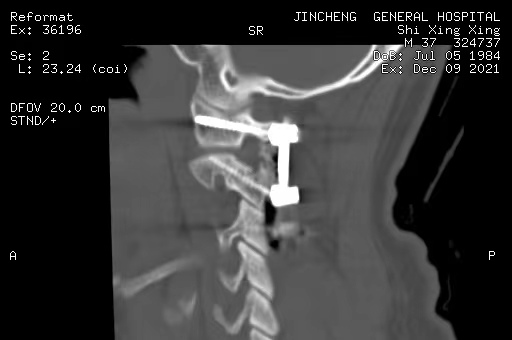

寰樞椎的內(nèi)固定治療、脊柱脊髓病損的手術(shù)治療

打破了脊柱手術(shù)生命禁區(qū)的限制,手術(shù)數(shù)量及質(zhì)量全市第一,處于省內(nèi)領(lǐng)先水平。